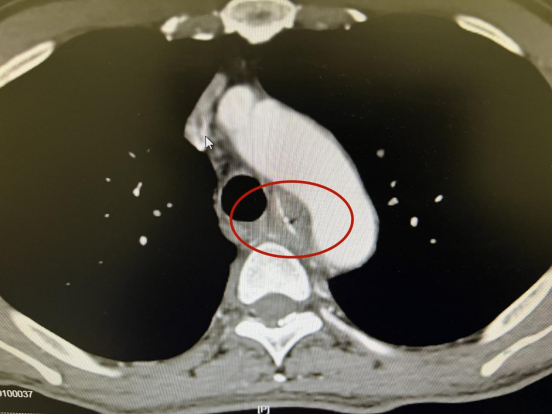

66岁的患者文先生(化名)3月初在北京出差时感觉鱼刺卡喉,喉咙不适。13日,文先生在北京某医院确诊为鱼刺卡喉,未予治疗。14日,他来到中南大学湘雅三医院耳鼻咽喉头颈外科门诊就诊。当时,文先生自诉7天前误吞一根鱼刺,当即胸骨上窝出现持续性刺痛,自行采用“喝醋疗法”后,疼痛症状未见明显改善,且随之出现吞咽困难。门诊医生为其进行胸主动脉CTA检查,即使用增强造影剂进行CT检查,以明确主动脉宽度,判断有无狭窄、有无夹层动脉瘤、有无主动脉扩张等病变。结果显示,患者主动脉弓轻度粥样硬化,T4-6椎体水平有异物穿透食管壁,离主动脉弓仅2毫米,情况十分危急,医生建议住院治疗。

14日上午10时左右,文先生办理住院手续后,耳鼻咽喉头颈外科副教授蒋明迅速召集心胸外科、呼吸与危重症医学科、消化内科会诊。患者进一步检查发现,鱼刺穿透食管壁,直逼主动脉弓,并向腔外延伸,手术难度及风险极大。经多学科会诊讨论,决定为患者实施胃镜下异物取出术,由心胸外科、消化内科专家同台手术治疗。考虑到患者情况危急,多学科专家团队在14日晚,紧急为其进行急诊手术。

手术过程中,可见距门齿26厘米处有一片状鱼刺嵌入食管壁内,与心脏同频搏动。专家凭借精准的控镜能力,通过反复调整异物钳角度及方向,最终以最小的前推力牢固钳夹住了鱼刺尾端,顺利将鱼刺取出,并为患者进行了食道瘘清创及金属支架置放术。手术历时25分钟,患者全麻清醒后诉胸痛感消失。术后,护理团队根据营养科制定的个性化营养方案,通过胃肠管为患者进行肠内营养治疗,保证患者的能量供应。目前患者恢复良好,但因鱼刺卡喉时间过长,存在感染等症,还将接受后续治疗。